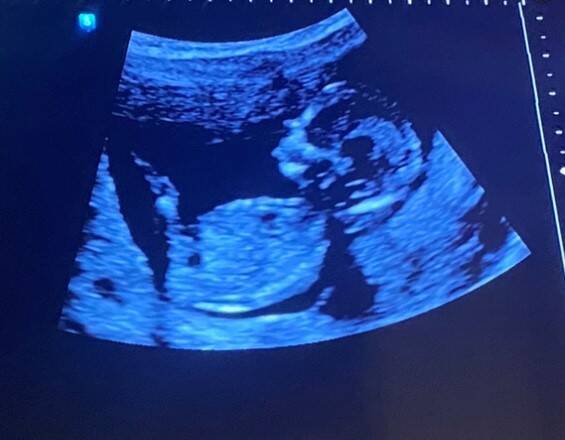

Altijd als ik weer een blog begin, dan lees ik de vorige blog nog even door. Maar jeetje, wat is die eigenlijk lang geworden, terwijl ik nog zoveel meer te vertellen had. En wat veel spelfouten, haha. Die moet ik nog maar even gaan rechtzetten, nadat deze blog klaar is. Misschien kom ik in deze blog nog wel terug op de dingen die ik de vorige keer nog had willen zeggen maar niet gelukt is. Zal ik maar direct met het goede nieuws beginnen?π De 13 weken echo was goed! Wat fantastisch. Het geeft natuurlijk nog geen garantie dat alles goed verloopt en dat alles goed gaat, maar die heeft niemand uiteraard! Alles zit er erop en eraan! Deze kleine steekt zelfs de tong uit, dat je zie ook heel duidelijk op de foto! Nu al een grapjas! Tenminste de verloskundige zei dat hij zijn tong uit stak. Ik denk overigens nu dat het een jongetje wordt. Na deze echo is mijn gevoel 100% omgeslagen. (Nu bijna 15 weken zwanger)